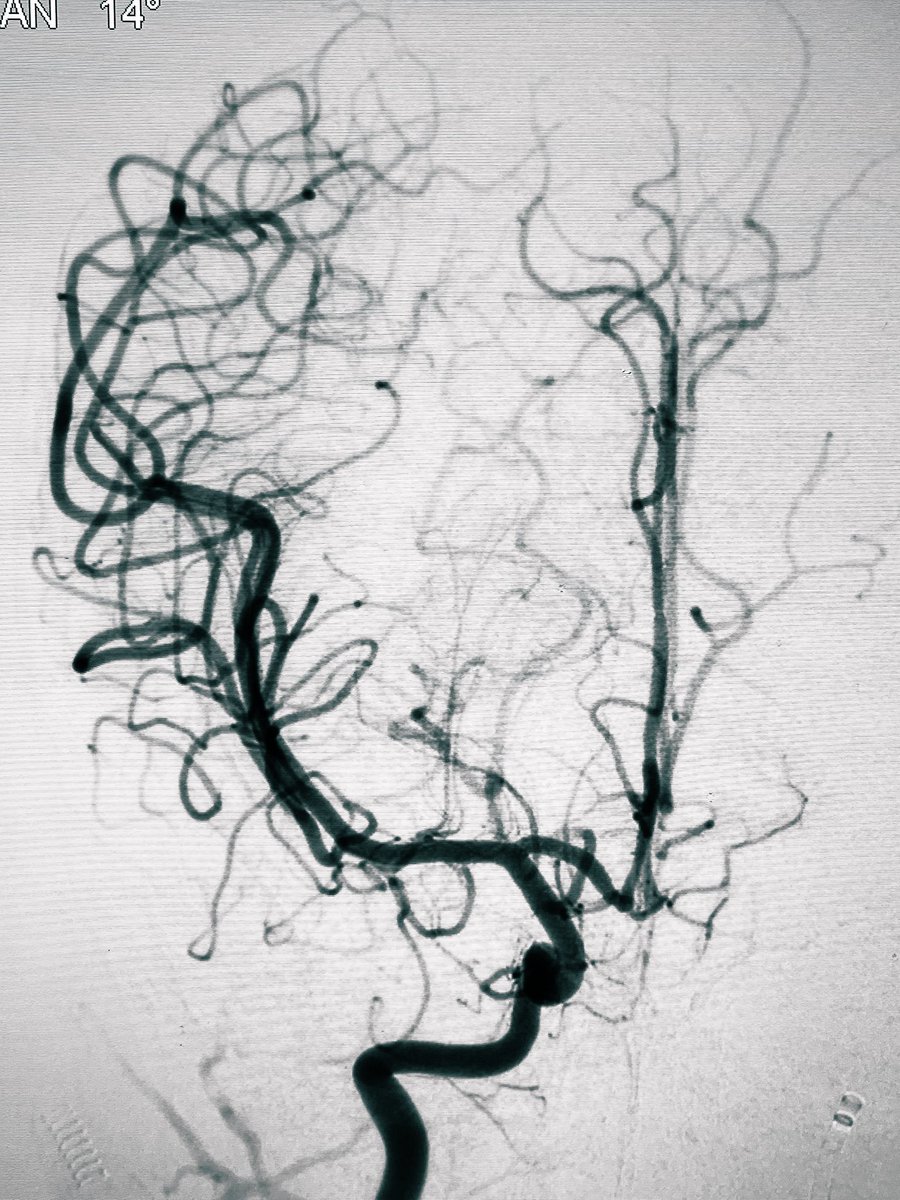

Cognard Type IV dAVF - complete embolization. Reaching the foot of the draining cortical vein is always challenging, but it has to be achieved before injecting the embolic agent.